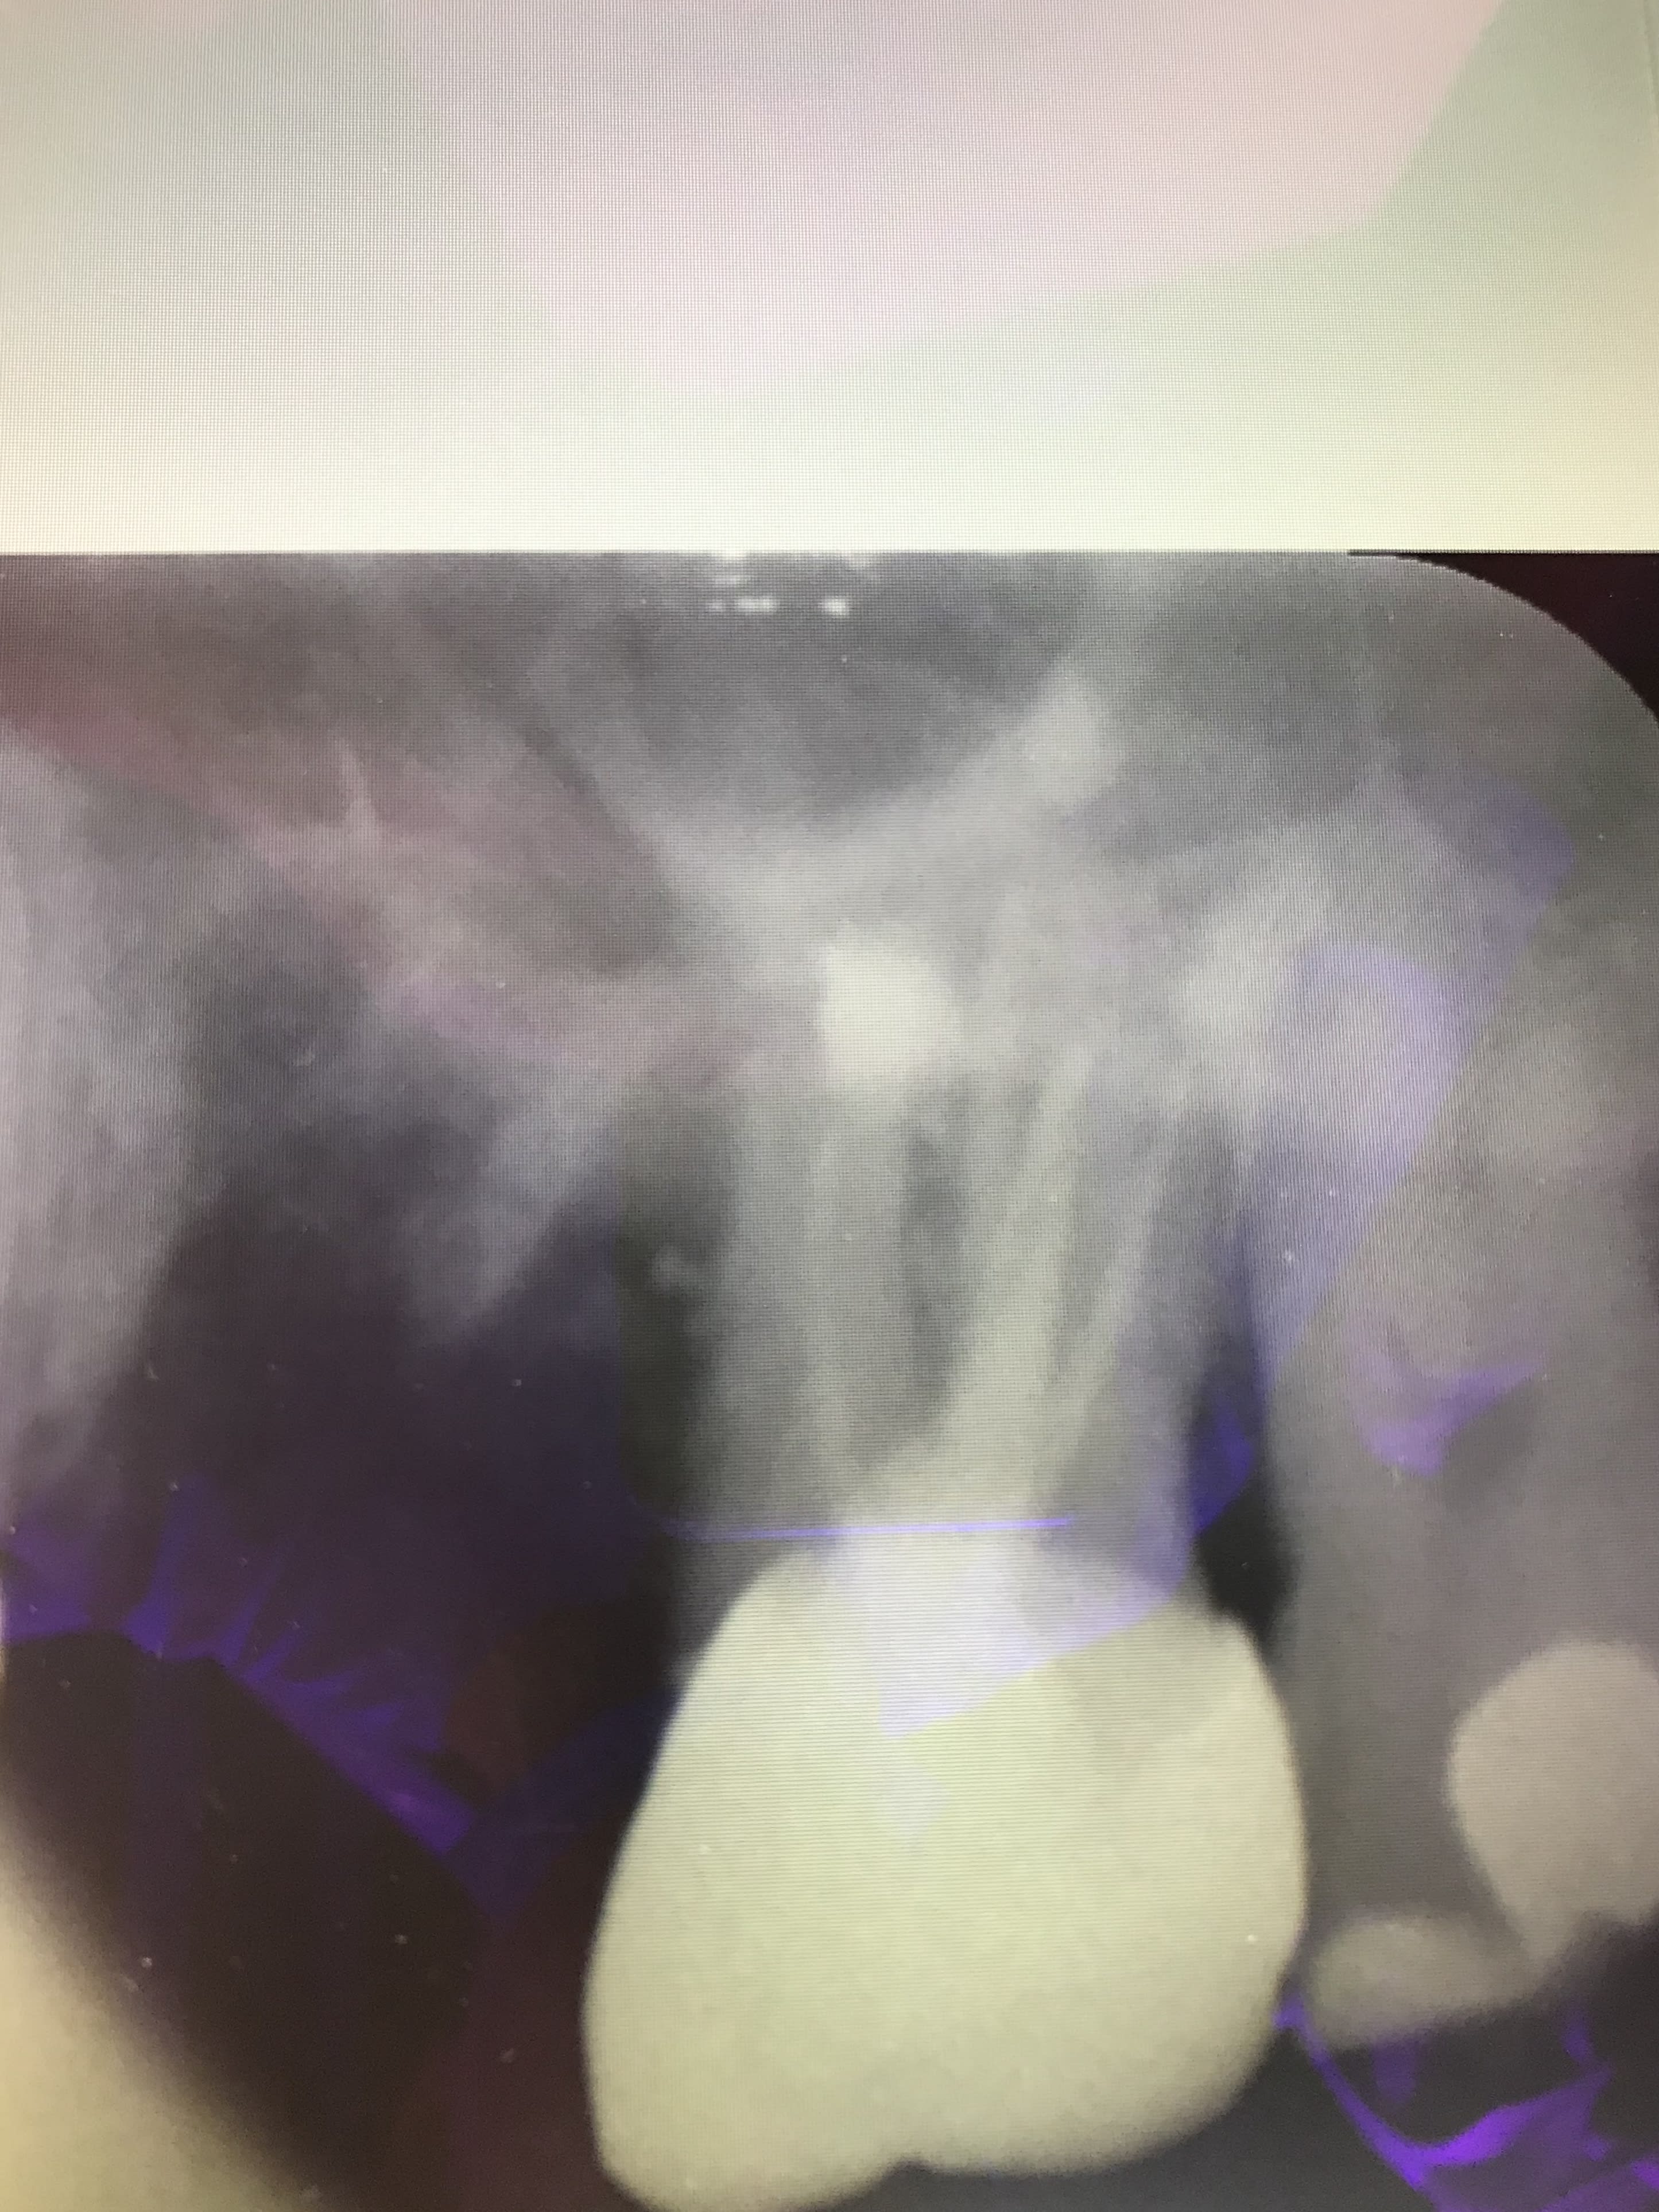

oh putaing qu'est ce que je fais ?

- j'ai déjà posé des implants sur ce patient et l'os c'est du béton armé donc pas d'ERI sinon la racine va casser

- tout le 1/3 apical est calcifié , impossible de passer le moindre instrument

- du coup je lui recrée un canal au milieu avec mes inserts :))

1 qbmcnk - Eugenol

3 biagxf - Eugenol

Capture d écran 2018 05 16 à 21.30 - Eugenol

Bin moi Junior quand je grossis la radio post op, je vois une fracture milieu de racine mais je dis ça, jdis rien :)))

Non a mon avis c est un artefact numerique.

T'es sûr ??? car ça ne concerne que cette dent et avec des inserts c'est possible, nan ???